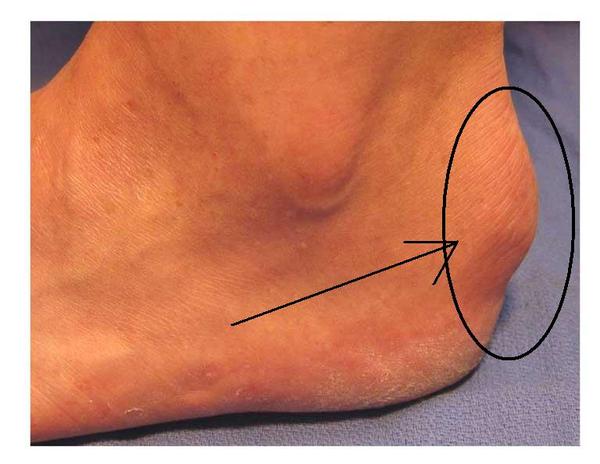

Dans les formes caractéristiques, la formation calcanéenne est responsable d’une déformation visible du talon « à l’œil nu » entraînant même, dans certains cas extrêmes, une irritation cutanée et des bourses rétro-achiléennes sur un contrefort de chaussures un peu rigides.

je travail en restauration et je suis donc souvent debout et je marche beaucoup et à chaque fois des grosseures comme sur la photo apparaissent à mes deux tendons d achille. cela ne me fait pas particulièrement mal mais cela devient gênant car alors mes chaussures ( ballerines) deviennent plus « petites » dut à la grosseur sur l’arrière du pied ce qui empire par des ampoules etc cela est il un signe de la maladie ou juste à un frottement trop important chaussure-talon ?